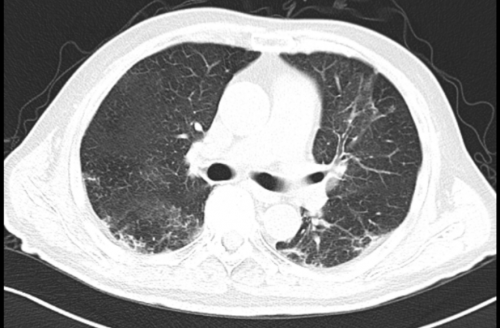

治疗后复查(11-14)

患者复查炎症指标下降,氧和较前好转,肺部CT示双肺渗出性病灶明显吸收,患者从经鼻高流量吸氧过度到鼻导管吸氧,最后能够完全脱离给氧装置,予以出院。